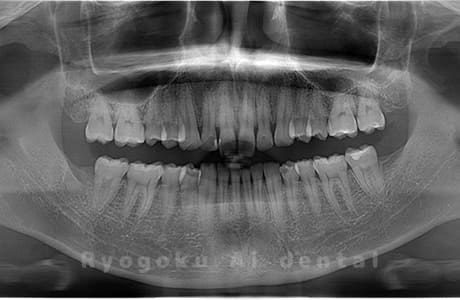

Case03

- 原因

- 上顎、下顎の親知らず

- 治療内容

- 上下4本の親知らずを抜歯したケースです。

<リスク・副作用>

手術後は痛み、腫れ、痺れなどの副作用が生じる場合があります。